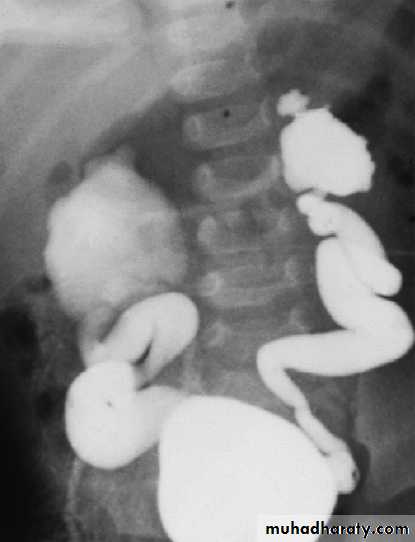

Intravenous urography (IVU)

Involves taking serial plain X-rays immediately before and after an intravenous injection of contrast medium. It has largely been replaced by ultrasound, CTKUB and CTU .

Pyelography

Direct injection of contrast medium into the collecting system from above or below. Antegrade pyelography

requires the insertion of a fine needle into the

pelvicalyceal system under ultrasound or radiographic

control. This approach is much more difficult and hazardous

in a non-obstructed kidney. In the presence of obstruction, percutaneous nephrostomy drainage can be established, and often stents can be passed through any obstruction. Retrograde pyelography can be performed by inserting catheters into the ureteric orifices at cystoscopy.